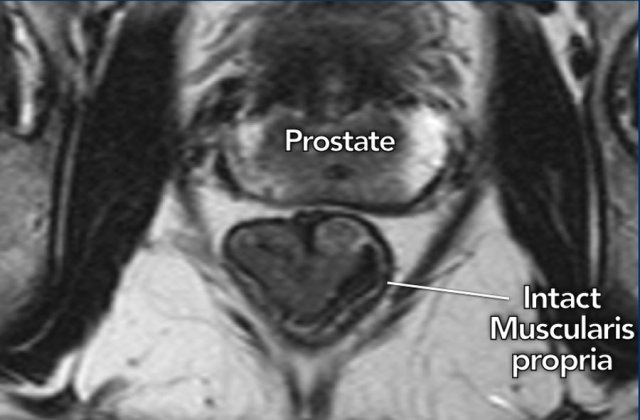

T1-T2 – limited to the bowel wall

T1

and T2 tumors are limited to the bowel wall and have a relatively good

prognosis.

The key finding to ensure that a tumor remains limited to the

bowel wall (T1-2) is the presence of an intact muscularis propria, which can be

recognized on MRI as an intact hypointense line surrounding the rectum.

Image

A cT1-2 tumor in the distal rectum is shown with an intact muscularis

propria, which is clearly recognizable as a hypointense outer line of the

rectal wall.